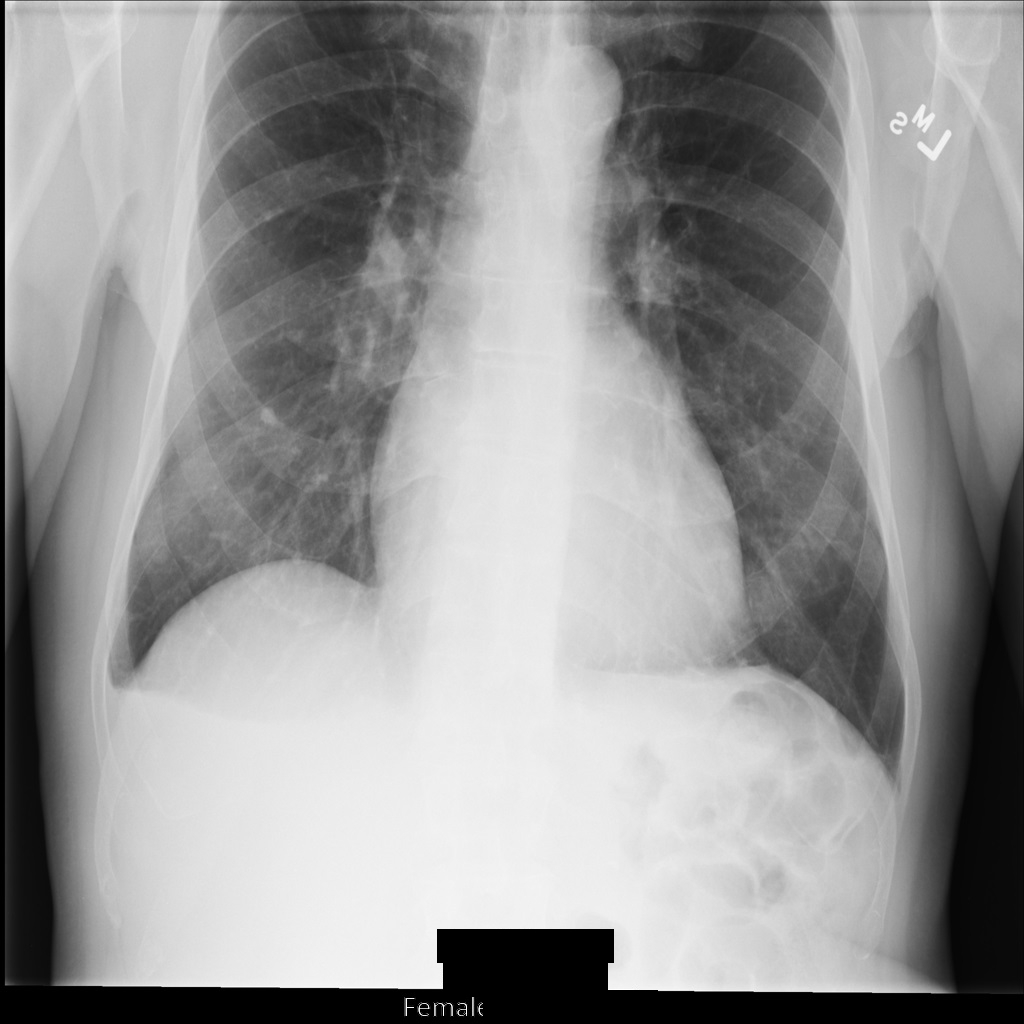

REDACT_SENSITIVE_TEXT_CLEAN_DESCRIPTORS를 사용하여 이미지를 익명화하면 이미지는 다음과 비슷합니다. 이미지 하단의 번인 텍스트가 일부만 수정된 것을 볼 수 있습니다. PatientSex (0010,0040)이 기본 DICOM infoType 중 하나가 아니므로 Female 텍스트가 계속 표시됩니다.

REDACT_SENSITIVE_TEXT_CLEAN_DESCRIPTORS를 사용하여 익명화한 후의 DICOM 인스턴스DICOM 태그 익명화